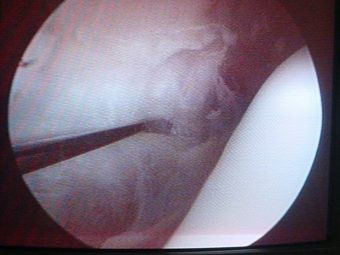

Luxación Habitual de Rótula

Envíado por Dr. Eduardo E. Martínez Melara